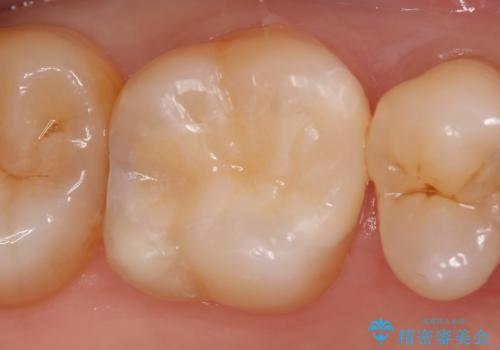

虫歯を除去後、セラミックインレーによる修復を行いました。

当院のセラミックインレーはemaxという強度と審美性に優れた材料を使用しています。

またプレス方式でインレーを製作しているため、削り出しで製作するCADCAMより優れた適合性も持ち合わせており、虫歯が再発しにくい修復物です。